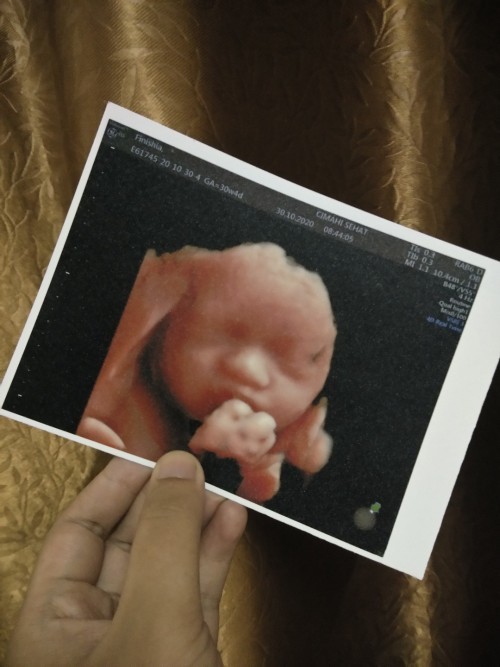

tangannya nutupin mulut huhu

mirip ga